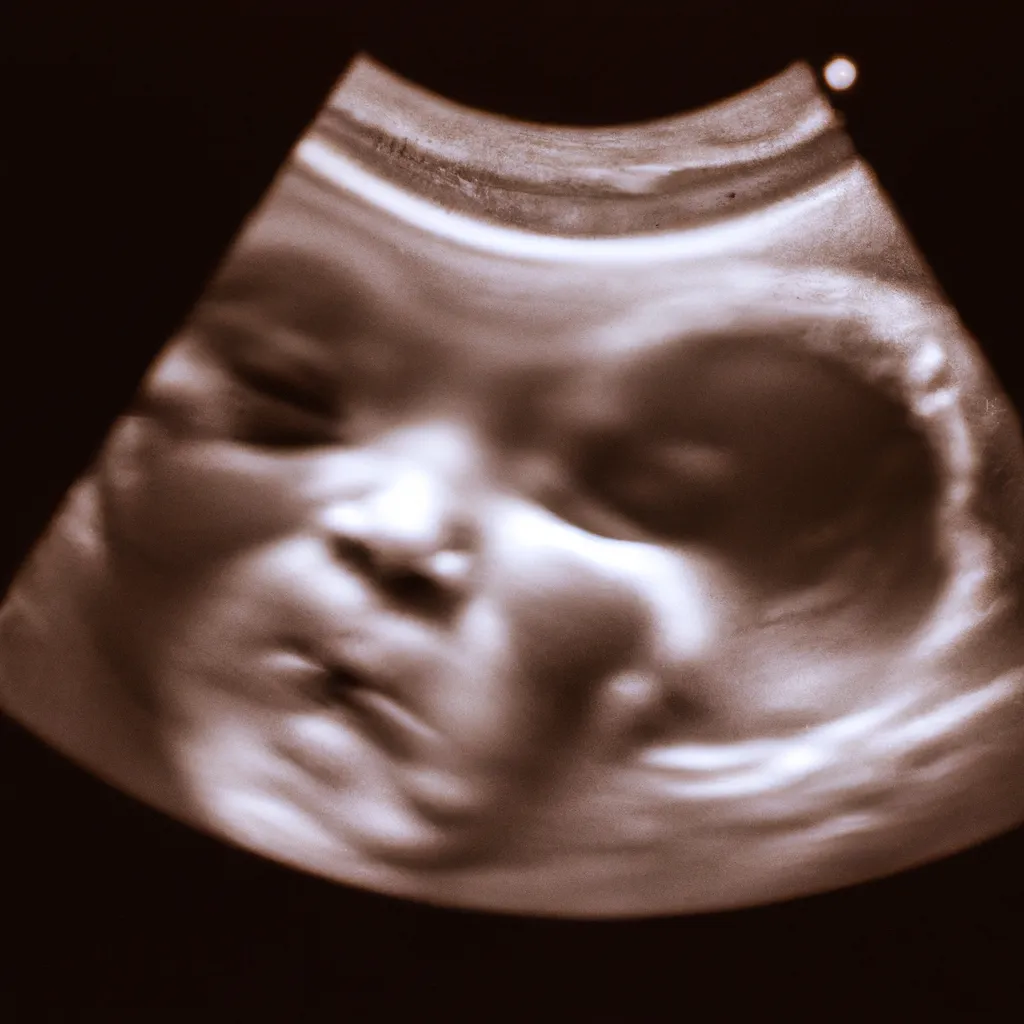

Główka dziecka zaczyna się kształtować już na bardzo wczesnym etapie ciąży. W pierwszych tygodniach po zapłodnieniu, zarodek przechodzi przez intensywne podziały komórkowe, które prowadzą do formowania się podstawowych struktur ciała. W okolicach trzeciego tygodnia ciąży, zaczyna się tworzyć cewa nerwowa, która później przekształca się w mózg i rdzeń kręgowy. W kolejnych tygodniach, około szóstego tygodnia, zaczynają się formować pierwsze zarysy główki. Proces ten jest niezwykle skomplikowany i wymaga precyzyjnej koordynacji wielu czynników genetycznych i środowiskowych.

Pierwsze zarysy główki dziecka zaczynają się formować około szóstego tygodnia ciąży.